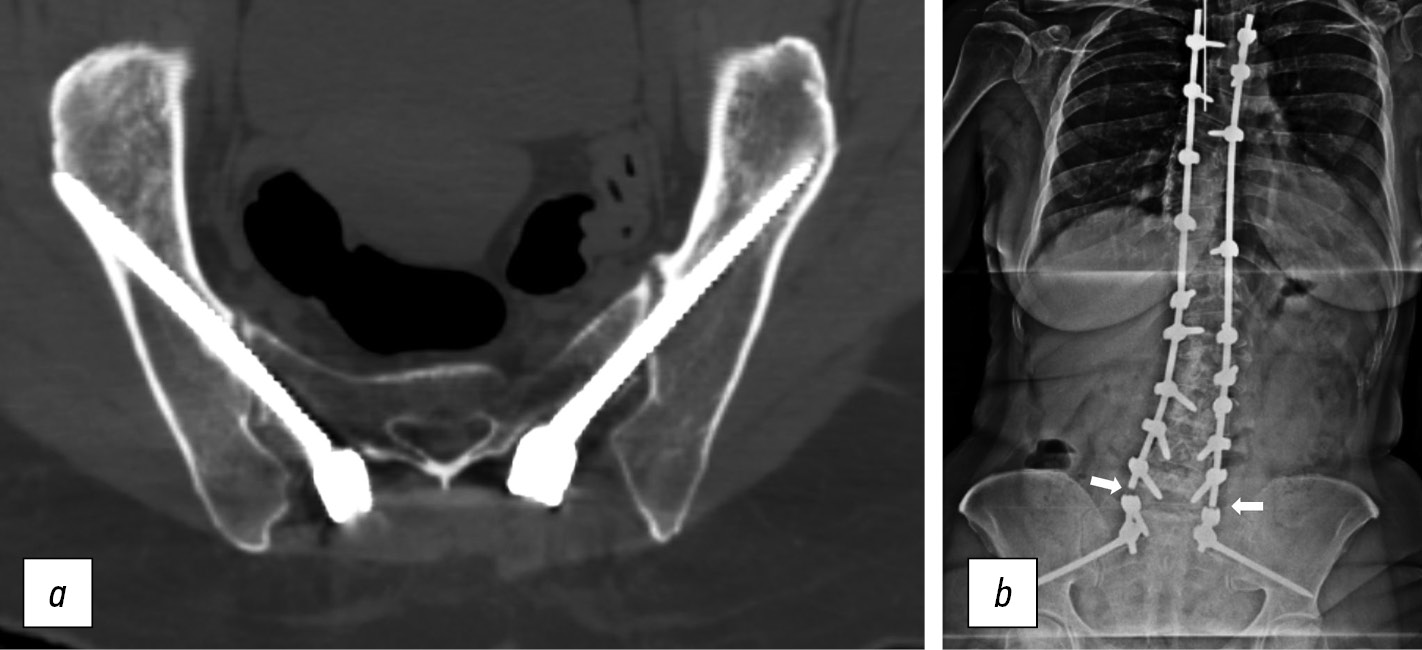

Далее после выполнения запланированных в зависимости от конкретной клинической ситуации этапов операции по декомпрессии невральных структур, выполнения корригирующих остеотомий и т. п. производили соединение установленных на поясничном и грудном отделах винтов с подвздошными винтами и окончательная коррекция деформации с последующей фиксацией в исправленном положении (рис. 1).

Рис. 1. Пациентка К., 21 год. Диагноз: «Врожденный левосторонний грудопоясничный кифосколиоз». Операция: резекция полупозвонка Т12–L1, дорсальная коррекция деформации и позвоночно-тазовая фиксация методом S2AIS: а — рентгенограмма до операции; b — компьютерно-томографическая реконструкция после операции

Fig. 1. Patient K., 21 years old. Diagnosis: Congenital left-sided thoracolumbar kyphoscoliosis. Operation: resection of the T12-L1 hemivertebra, dorsal deformity correction and spinopelvic fixation using the S2AIS method: a — radiographs before surgery; b — CT reconstruction after surgery